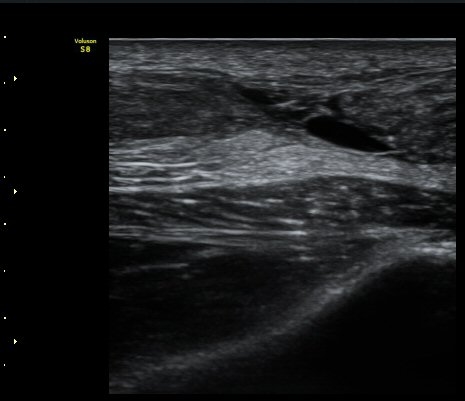

ÃÊÀ½ÆÄ °Ë»ç

d